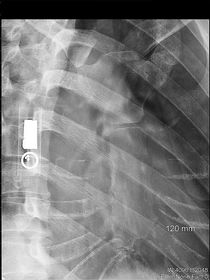

| PA Ribs Above Diaphragm Unilateral | patient rotated towards the right |

| AP - LPO Ribs Above Diaphragm Unilateral | Insufficient obliquity |